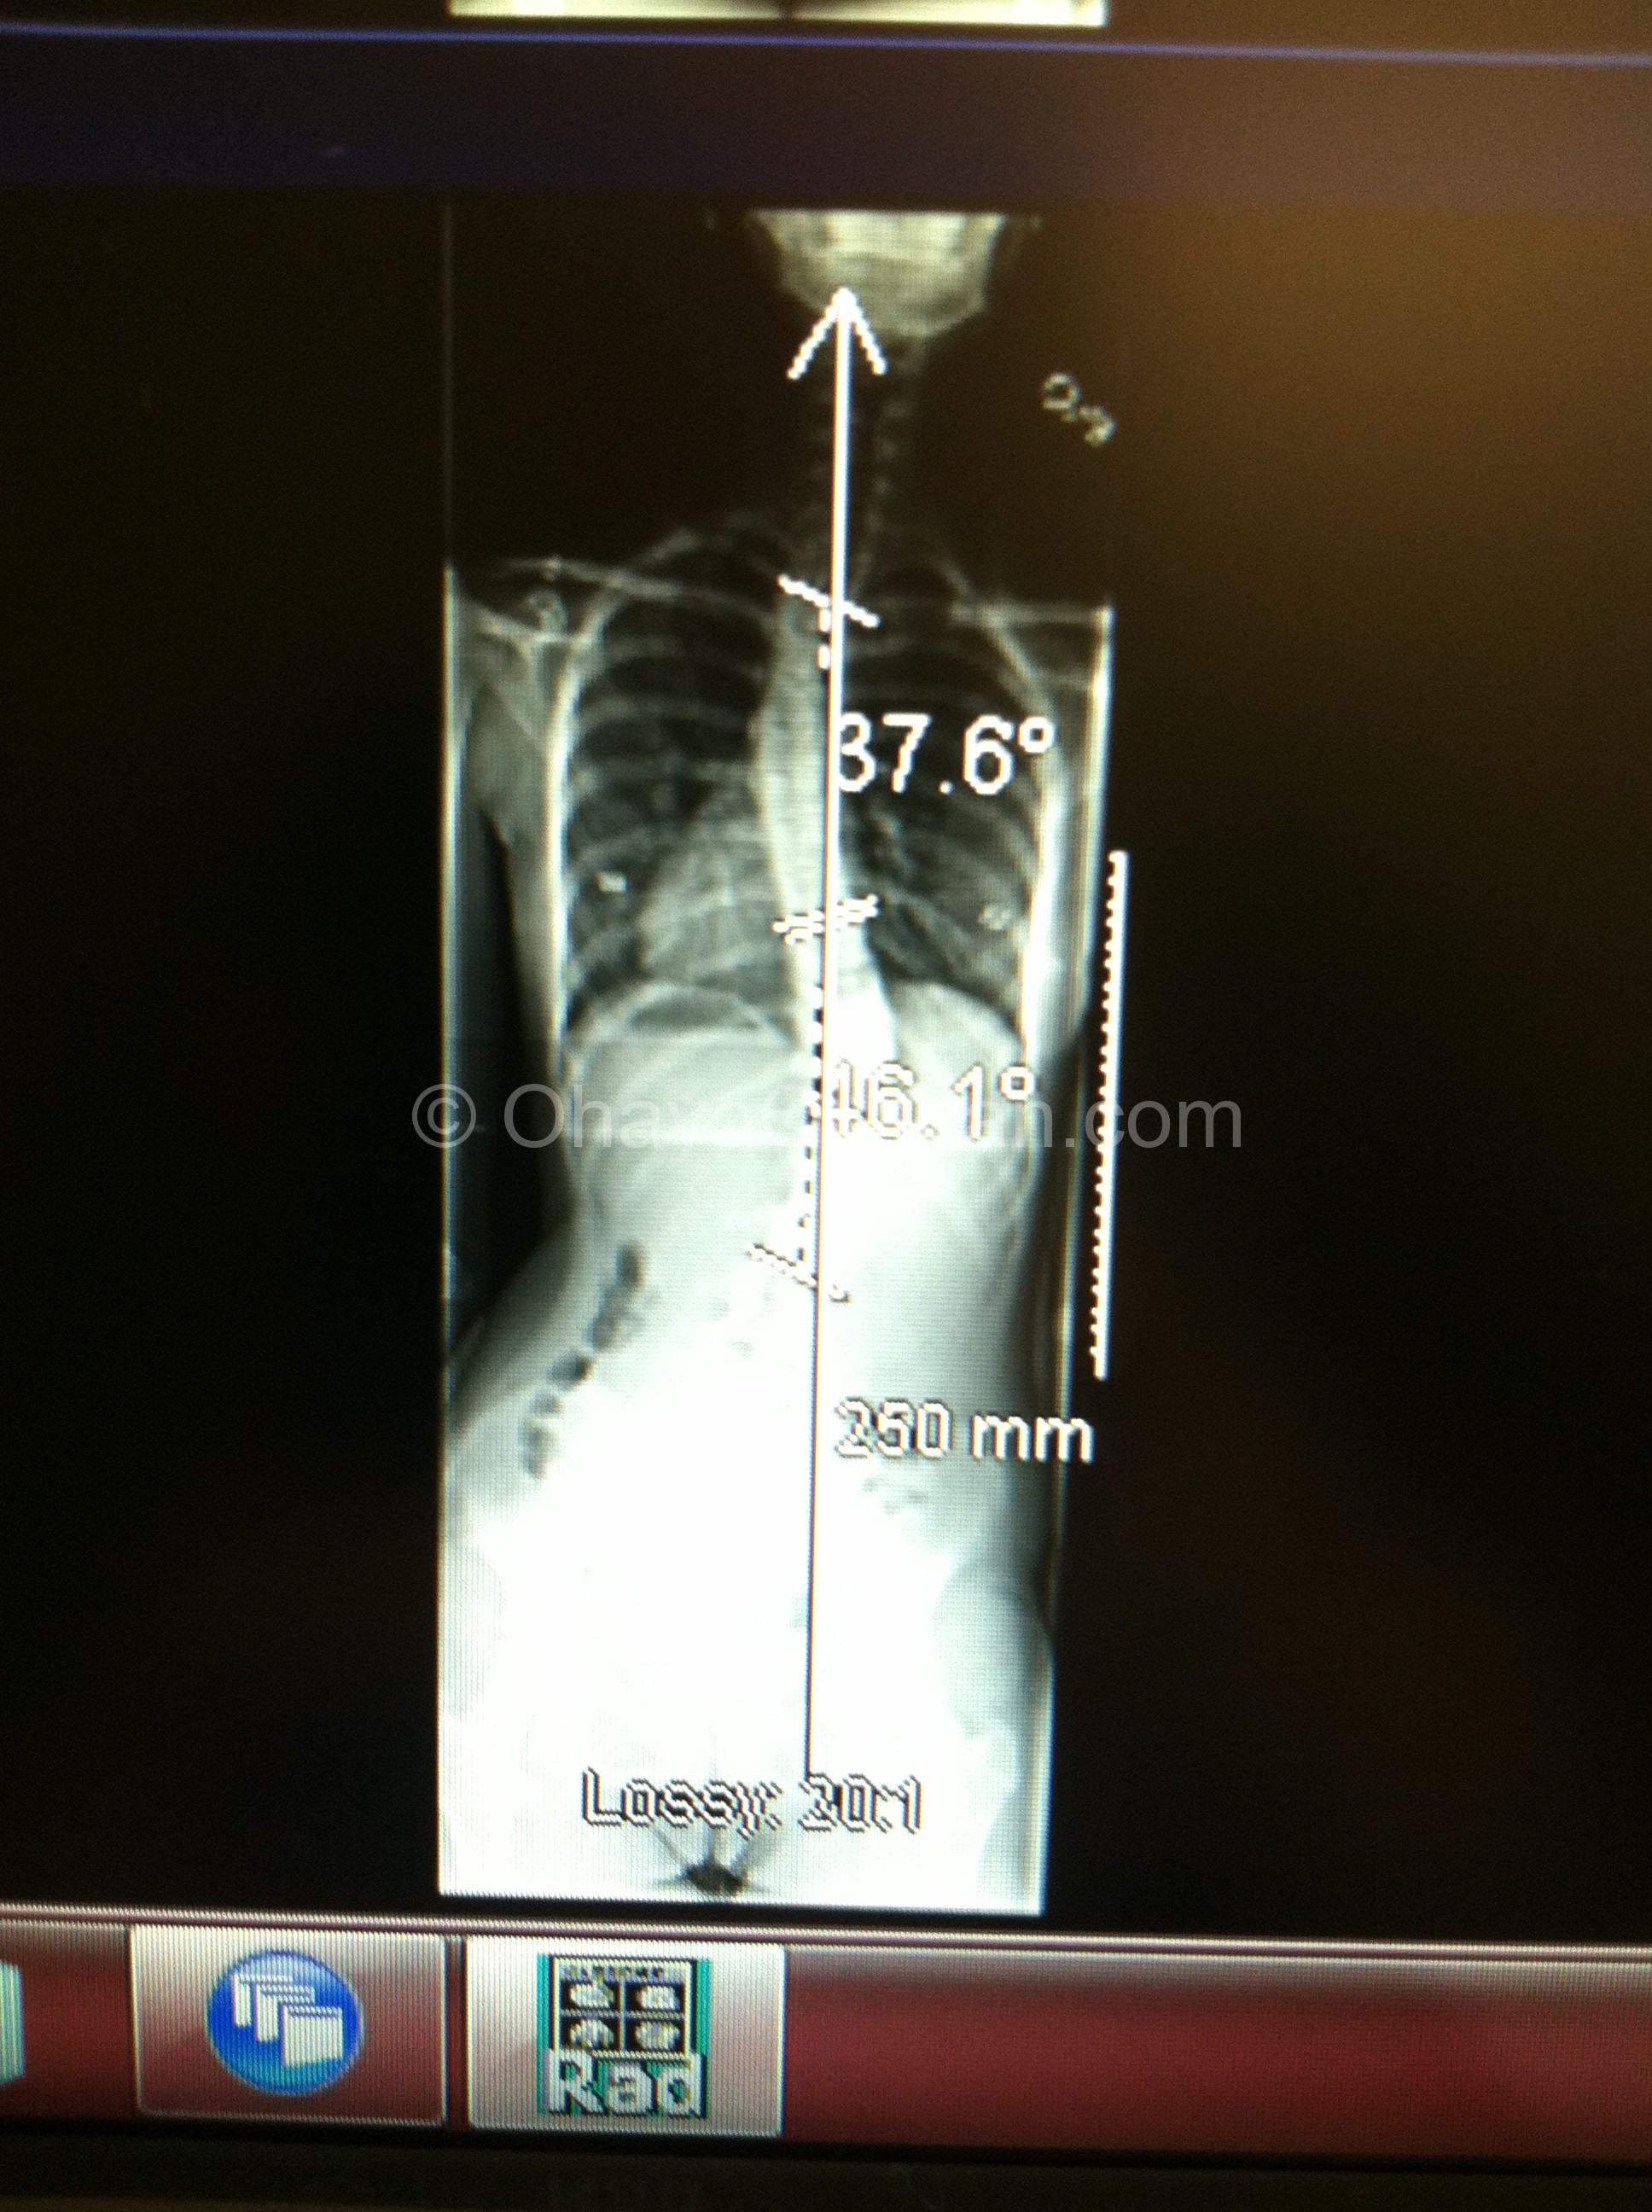

It’s a crummy cell phone pic, but in the above you can see her spine before the surgery. 38* and 45* causing some problems with her lung, shoulders, waist, and balance. You can see how it throws off her neck too.